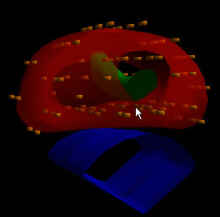

Photo: A radiation treatment plan for multi-catheter breast brachytherapy.

Breast brachytherapy is used for accelerated partial breast treatment. Traditional radiation therapy for breast cancer involves approximately six weeks of daily external treatments. Some women are candidates for partial breast treatment, which is a promising new treatment delivered over just five days. Several methods of partial breast treatment are available at Massey, including multi-catheter implants, both the Contura and MammoSite devices, and three-dimensional conformal external beam therapy.